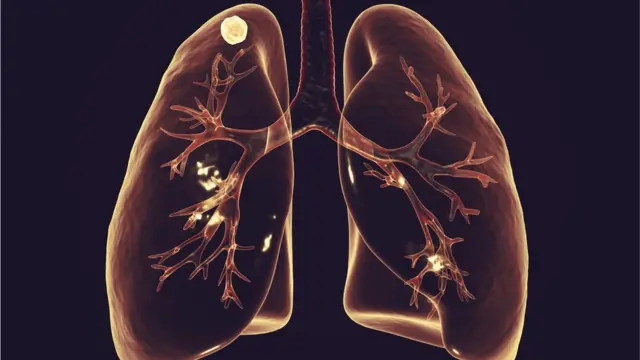

যক্ষ্মা যেভাবে হয় এবং যেসব অঙ্গ আক্রান্ত করে

যুক্তরাষ্ট্রের রোগ নিয়ন্ত্রণ বিষয়ক সংস্থা সিডিসি বলছে যক্ষ্মা খুবই সংক্রামক। মাইকোব্যাক্টেরিয়াম নামে একটি ব্যাকটেরিয়ার কারণে যক্ষ্মা হয়ে থাকে। সংক্রমিত ব্যক্তির সংস্পর্শে এলে, তার হাঁচি, কাশি বাতাসে ছড়িয়ে পড়লে আশপাশের মানুষ আক্রান্ত হতে পারেন। কথা থেকেও বাতাসে যক্ষ্মার জীবাণু ছড়িয়ে পড়তে পারে।

একজন মানুষের কফ ছায়াহীন জায়গায় ফেললে বহুদিন জীবাণু বেঁচে থাকে। অপরিচ্ছন্ন, বদ্ধ, আলো বাতাসহীন ঘরে এটি বেশি ছড়ায়। এক ঘরে বেশি মানুষ থাকলে এটি দ্রুত ছড়ায়। বিভিন্ন রকমের যক্ষ্মা রয়েছে।

যে যক্ষ্মা ফুসফুসের ক্ষতি করে সেটি পালমোনারি টিউবারকিউলোসিস। টিবি মেনিনজাইটিস-কেন্দ্রীয় স্নায়ুতন্ত্রকে আক্রান্ত করে। হাড় আক্রান্ত করে এমন যক্ষ্মাকে বলা হয় স্কেলেটন টিবি বা পটস ডিজিজ। এটি শরীরের গিট ও হাঁটু আক্রান্ত করে।

এছাড়া এক প্রকার যক্ষ্মা রয়েছে লিম্ফনোড টিবি যা লসিকা গ্রন্থিকে প্রভাবিত করে। খুব বেশি খারাপ পর্যায়ে গেলে যক্ষ্মা মস্তিষ্কে ছড়িয়ে পড়তে পারে। এতে শিশু মানসিক ও শারীরিক প্রতিবন্ধী হয়ে যেতে পারে। চোখ ও কানসহ গুরুত্বপূর্ণ অঙ্গের সমস্যা দেখা দিতে পারে। যক্ষ্মা শরীরের সকল অঙ্গের ক্ষতি করতে পারে।